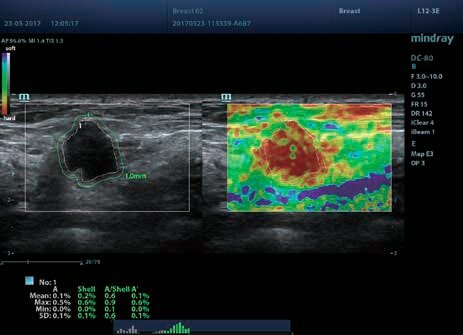

Клинические изображения

- Эластография сдвиговой волны – количественное измерение жесткости ткани и выявление новообразований.

Функции ультразвукового аппарата Mindray DC-80 X-Insight: PSH, iBeam, iClear, iTouch, iWorks, iNeedle iZoom, iScanHelper, Echo Boost, HR Flow, Depth VR, Smart Track, Smart3D, 4D, Smart-V, Auto IMT, Auto EF, Free Xros M, Free Xros CM, STIC, Color 3D, Stress Echo, TDI, TDI QA, Niche, iLive, iScae View, STE, STQ, MedTouch, компрессионная эластография, эластография сдвиговой волны, контрастные исследования и другие.